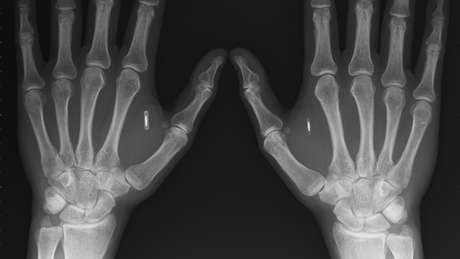

Segundo a agência de notícias fancesa AFP, de 2015 até agora, já são mais de 3 mil pessoas na Suécia que possuem ao menos um microchip subcutâneo implantado em seus corpos. Os chips, que são

aproximadamente do tamanho de um grão de arroz e geralmente aplicados entre o indicador e polegar das mãos, ajudam a substituir diversos dispositvos que usamos cotidianamente, como cartões de

ônibus e metrô, as chaves de casa ou mesmo o registro de horas trabalhadas na empresa.

O procedimento de implantação subcutânea dos microchips é bastante semelhante aos chips que são implantados em animais de estimação, ou ainda os dispositivos hormonais usados desde a década de 1990 como método contraceptivo. Com uma pequena cânula, o modificador corporal insere o chip na mão do usuário, que poderá configurá-lo usando seu smartphone.